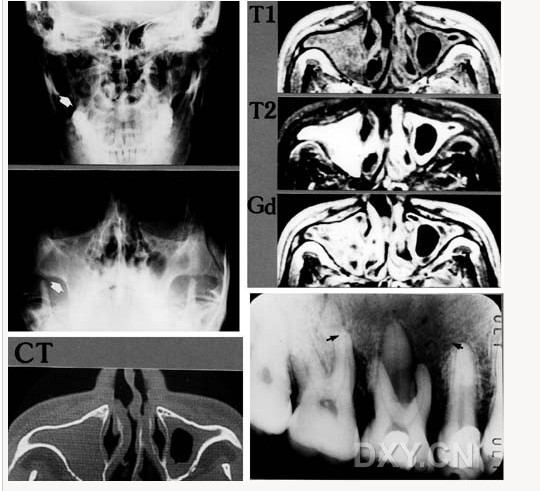

舍格倫綜合征

大理石骨?。ㄏ骂M骨有明顯的骨化影像,恒牙埋伏)

鼻竇炎(注意不要誤診呀)

良性成牙骨質(zhì)細胞瘤